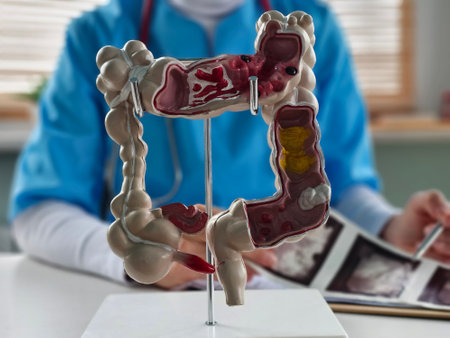

Doctor examines digestive system model and ultrasound image. Stomach intestine ulcers cyst and oncology and examination

Detailed anatomical model of the human digestive system displayed during a medical consultation in a clinic